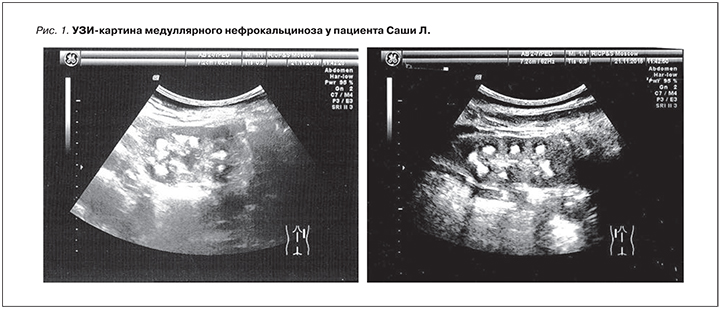

Морфология мочевого осадка: нейтрофилы – 69%, лимфоциты – 18%, эозинофилы – 13%. Обнаружены клетки эпителия с признаками атипии в большом количестве. По данным УЗИ почек выявлены утолщение и диффузные изменения почечной паренхимы, симптом «гиперэхогенных пирамидок», эхогенность коркового слоя значительно повышена, сравнима с эхогенностью печени. По периферии пирамидок эхогенность не изменена, что соответствует нефрокальцинозу второй стадии. Корковый слой истончен. Почки несколько увеличены в размерах (правая 5,3×3,4×2,8 см; объем – 26,6 см3, левая 5,9×3,7×2,6 см3; объем – 29,2 см3, соотношение объема почек и массы тела: 0,73% норма (0,4– 0,7)% (рис. 1).

При допплерографическом исследовании сосудов почек выявлены пониженная систолическая скорость кровотока на уровне почечных, сегментарных, долевых артерий обеих почек и повышенные показатели периферического сопротивления на уровне почечных, сегментарных, долевых артерий обеих почек.